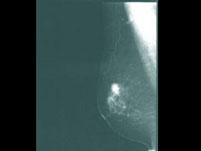

乳腺癌的X线表现为()A.密度增高肿块影B.边界不规则C.可有钙化点D.钙化点不密集E.颗粒大

问题 乳腺癌的X线表现为()

选项 A.密度增高肿块影 B.边界不规则 C.可有钙化点 D.钙化点不密集 E.颗粒大

答案 ABC